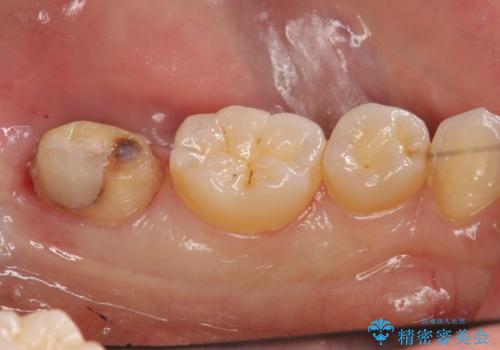

虫歯を取ると、歯ぐきの奥深くまで虫歯になっており、そのままではきちんと修復することが難しい状態でした。

①虫歯を無視してとりあえずつめる(必ず虫歯になり、進行するため神経を取らなければいけなくなる)

:マージン(キワ)はぴったりは合わないため、長期的な予後は見込めない。=歯は長く持たない。

②歯周外科手術を行う。しっかり歯ぐきを下げ、マージンが歯肉縁下深くならないようにする

:虫歯も取り切って、きわがあったものが入るため①のようなことは起こりにくい。しかし外科処置が必要。

1:つめてあったセメントを除去、虫歯除去、セメントを再度つめる。処置後神経に問題がなければ手術の予約を取る。